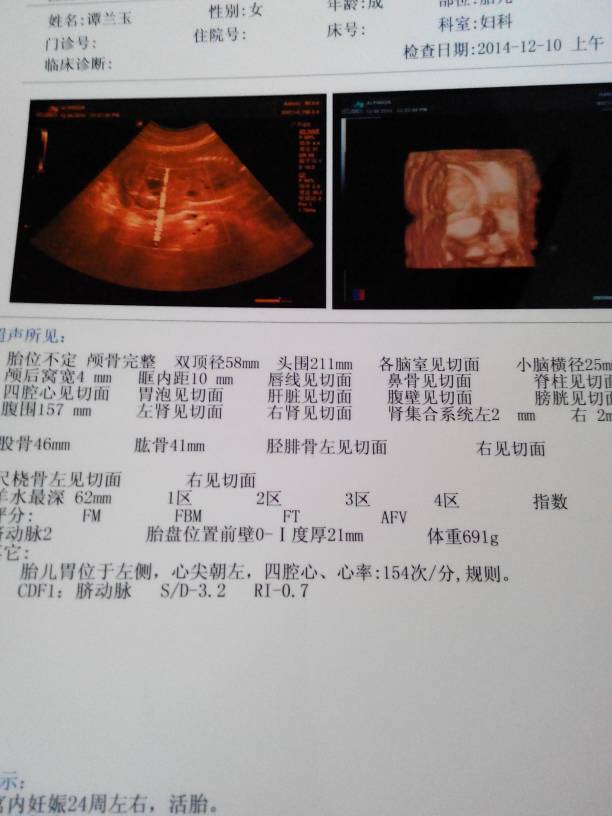

刚做的四维照,医生说宝宝很好,我终于放心了,宝妈们帮我看看是男还是女,挺好奇的

刚做的四维照,医生说宝宝很好,我终于放心了,宝妈们帮我看看是男还是女,挺好奇的。